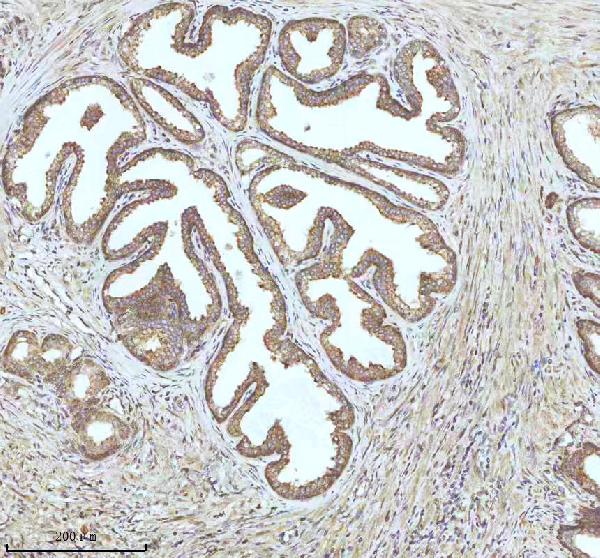

IHC (Immunohiostchemistry)

(Figure 2. IHC analysis of IGFL3 using anti-IGFL3 antibody (AAA127880).IGFL3 was detected in a paraffin-embedded section of human prostate cancer tissue. Heat mediated antigen retrieval was performed in EDTA buffer (pH 8.0, epitope retrieval solution). The tissue section was blocked with 10% goat serum. The tissue section was then incubated with 2ug/ml rabbit anti-IGFL3 Antibody (AAA127880) overnight at 4 degree C. Peroxidase Conjugated Goat Anti-rabbit IgG was used as secondary antibody and incubated for 30 minutes at 37 degree C. The tissue section was developed using HRP Conjugated Rabbit IgG Super Vision Assay Kit with DAB as the chromogen.)